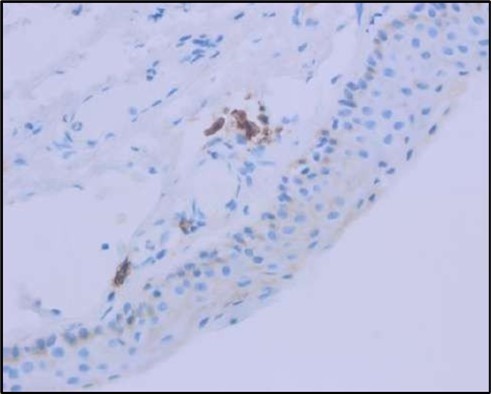

Figure 5c.OS, Immunohistochemical stain using CD45 (leukocyte common antigen) demonstrating a dense population of lymphocytes stained brown

Figure 5d.OS, Immunohistochemistry using CD138 showing many plasma cells (brown-stained) in the inflamed tissue.

Histopathological examination revealed a dense infiltration of CD138-positive plasma cells within the excised conjunctival tissue (Figure 5b, Figure 5c, Figure 5d). This finding supports an antibody-mediated immunopathogenesis in Mooren’s ulcer, consistent with Type II and Type III hypersensitivity mechanisms described in the literature 20, 21. The prominent presence of CD138- positive plasma cells provide a clear pathological rationale for conjunctival resection, as excision of the immunologically active perilimbal conjunctiva effectively removes the local 'factory' of autoantibodies that drive corneal stromal destruction, thereby halting ongoing tissue damage 21.